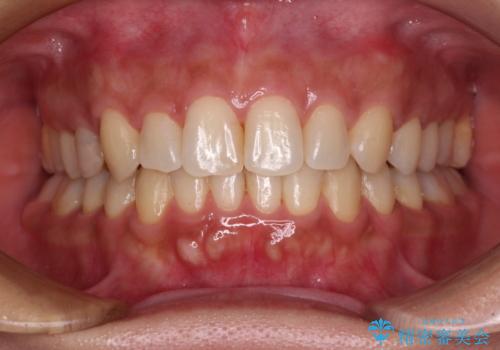

移動量が多かったため、治療期間は通常より半年~1年ほど長くかかりましたが、上下の正中をほぼ同じ位置にまで移動させることができました。